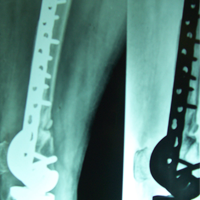

Case:13 Infected nonunion with implant failure

31 years old patient with fracture radius-ulna (1-year-old) with infected non-union was treated with implant removal & external fixation. ‘K’ wiring was done for distal radio-ulna joint stabilization. Bone grafting was done after 3 weeks. Fracture united 6 months’ post-operative.

Pre-Op

Post-op

Imm Post-op

Bone gratfing + ex fix

6 months post-op